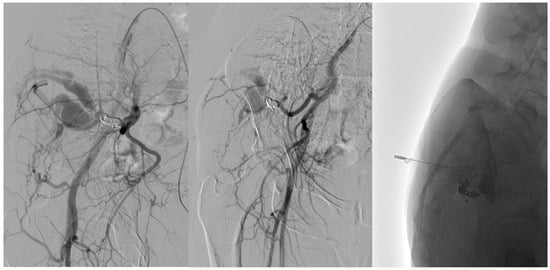

In recent years, treatment techniques have evolved, with trans-arterial embolization emerging as a preferred approach due to its lower complication rates and reduced recurrence [2,13,19,20,27,29,30]. However, recurrence remains a significant challenge, occurring in 25% of patients within the first year post-treatment and potentially up to 10 years later. Therefore, long-term follow-up is essential to detect recurrences. In our study, a single embolization session was sufficient to resolve the condition, with the highest success rate achieved through combined arterial and venous treatment. Specifically, the arterial side was treated using Onyx, PVA, or coils, while the venous side was treated via direct puncture with Lauromacrogol [Figure 4]. This combined approach was associated with a low recurrence rate (0%).

Figure 4. Following a 6-month ultrasound follow-up, there was evidence of recurrence from the collateral branch of the gluteal artery. The left image shows an angiographic examination performed pre-procedure after super-selective catheterization using a Progreat microcatheter. The center image shows post-embolization angiography performed by EVOH. The venous component was treated in the same session by direct puncture by injecting Atossisclerol.